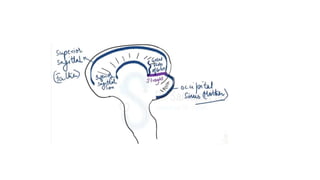

The document discusses lateral sinus thrombosis, also known as lateral sinus thrombosis or Otogenic suppurative thrombophlebitis, which is defined as the simultaneous presence of venous thrombosis and suppuration in the intracranial cavity. It is most commonly caused by b-hemolytic streptococcus and symptoms include nausea, vomiting, toxic and restless behavior, deep boring ear pain, and foul smelling blood tinged ear discharge. Management involves imaging, lumbar puncture of CSF to analyze volume, rate of formation, and composition.